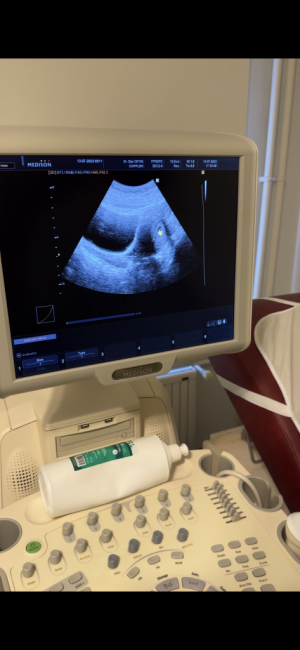

Hanımlar merhaba, son adet tarihim 29 Mayıs, adetten iki önce idrar testi silik beta 4.95, beklenen adet gününden bir gün sonra beta 125 ile gebelik takibini yaklasık 10 gün beta takibi ile yaptım, sırasıyla 477, 1456, 4045, 5400(bu değerde keseyi görmek için doktora gittim devlet hastanesinde kese gözükmedi idrarımı yaparak gittigimi sonradan fark ederek içim de rahat etmeyince başka bir doktora özele gittim orada kese görüldü ve bize 5haftalık dedi(tarih 13 temmuz.) SAT a göre 7haftalık gözüküyordu). 2 hafta sonra kalp atısı icin tekrar gelmemi istedi, fakat 20 temmuz günü fka göremedi (karın+vajinal usg) renkli ultrasona yonlendirip raporla gel haberler iyi değil dedi olayın şokundan gs kac cm embriyo ne durumda hiçbir sey soramadım, ertesi gün baska bir doktora bir de siz bakar mısınız kalp atışı duyamadık dedim baya inceledi(vajinal) o da göremedi bebek 7haftalık, anembriyonik gebelik? 1 hafta istersen bekleyelim diyip ultrasona yonlendirdi, transvaginal Usg deki doktor bebegin 6+3 gunluk oldugunu Gebelik kesesinin 18.3mm olduğunu, değerlendirmek icin cok kücük oldugunu soyleyip rapora haftaya tekrarı uygundur yazdı, tabiki üzüldüm kendimi en kötüsüne hazırlıyorum ama geç döllenme oldugunu varsayıp doktora ilk gittigim zaman o 5haftalık dediğinde acaba 4+3 oldugumu şimdi de 6+3 oldugumu normal oldugunu dusunmek istiyorum çünkü yolk kesesi mevcut kese var duzgun gorunuyor gibi fotoğraflarını ekledim, şimdi iki gün geçti kafamdan atamıyorum tekrar beta baktım 284320 çıktı acaba düşme var mı diye 3 gun sonra bakacagım, kalp atışının 8.haftaya kadar duyulabildiğini okudum bu forumlarda, bebeğin olmadığına dair özeldeki doktor bir sey demedi sadece kalp atısı yok dediler sizin bir fikriniz var mı lütfen yardımcı olur musunuz teşekkür ediyorum